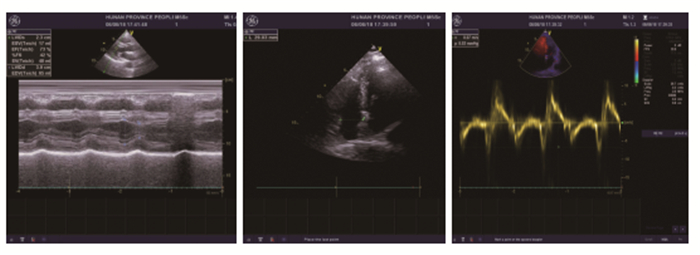

情况紧急,立即予以经静脉临时心脏起搏。团队紧急配合历时约3min完成经静脉临时心脏起搏安置:a(术者)穿好一次性无菌服,准备与打开中心静脉穿刺包,开始操作;b准备倒络合碘、撕血管鞘与起搏电极;c配肝素钠生理盐水;d连接心电图肢体电极,准备好桥接线连接起搏电极。在双极腔内心电图引导下,将临时起搏电极头端精准安置在右室心尖,并于心内膜恰当接触。设置起搏器参数如图 2:感知2~3mV之间,起搏3~5mA之间,频率60~70次/min之间(见图 2)[4]。连接起搏器与电极,同时将准备好的500mg艾司洛尔静脉推注100mg,继以200mg/h泵入,患者心率立即稳定下来,神志转清,艾司洛尔持续泵入,控制快速心室率,临时心脏起搏使得心率不低于设置的起搏频率(见图 3)。此时考虑患者为高危急性冠脉综合征,立即启动绿色通路,行急诊冠脉造影。检查报告结果提示:①冠状动脉分布:右冠优势型;②左主干:未见明显狭窄;③左前降支:近中段狭窄40%,中段收缩期狭窄50%,舒张期无狭窄,远端未见狭窄,第一对角支未见狭窄,远端血流TIMI3级;④左回旋支:较细小,远端狭窄50%,钝缘支未见狭窄,远端血流TIMI3级;⑤右冠状动脉:近段未见狭窄,中段未见狭窄,远段未见狭窄,后侧支远段狭窄60%,后降支未见狭窄,远端血流TIMI3级。冠脉造影结果与前次入院比较并无特殊变化,故考虑本次事件为心肌桥狭窄引起,未植入支架,继续强化药物治疗。当日造影术后查心脏彩超显示心功能正常(见图 4)。次日清晨抽血查肌钙蛋白(CTnI)0.163ng/mL(参考范围 < 0.034 ng/mL),BNP240pg/mL。3日后复查CTnI正常。拔除临时起搏器,患者住院1周后出院。

|

图 4 注:心脏彩超提示左房增大,室间隔增厚,EF值73%。 |